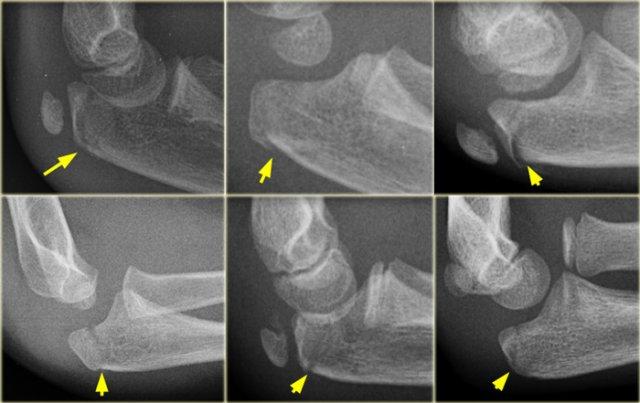

The radial epiphysis is slipped (arrows). The radiocapitellar line does not pass through the capitellum indicating dislocation and there is a fracture of the olecranon

Gãy cổ xương quay cũng như trật đầu xương quay trong 50% trường hợp có liên quan đến các tổn thương khuỷu tay khác.

Thường gặp nhất là gãy mỏm khuỷu.

Khi đầu xương quay còn rất nhỏ, trượt đầu xương quay có thể bị bỏ sót (hình).

LEFT: an obvious radial dislocation. No fracture of the ulna (Monteggia) was foundRIGHT: a subtle radial head dislocation. Associated olecranonfracture is seen on carefull inspection

Trật khớp đầu xương quay có thể rất rõ ràng.

Tuy nhiên, không hiếm trường hợp những trật khớp này khó nhận thấy và dễ bị bỏ sót.

Trong mọi trường hợp, cần tìm kiếm các tổn thương kèm theo.

Trong mô tả ban đầu của Monteggia, có sự trật khớp đầu xương quay kết hợp với gãy thân xương trụ đoạn gần.

Tuy nhiên, gãy xương ở bất kỳ vị trí nào dọc theo xương trụ cũng đã được ghi nhận.

Đặc biệt, gãy xương mỏm khuỷu kèm theo rất phổ biến (hình).